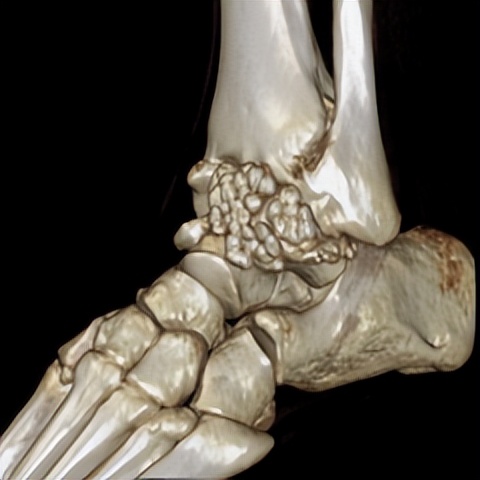

何河北制定了详细的手术方案,为患者开展踝关节镜下滑膜软骨瘤取出术+距腓前韧带重建术。他从患者踝关节中取出32颗“珍珠”(关节游离体),然后进行踝关节外侧韧带重建。

▲术后CT显示滑膜软骨瘤完全取出,韧带重建良好。